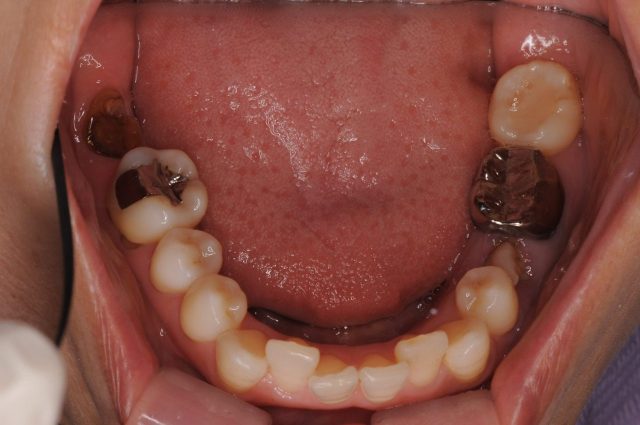

治療前

【治療前】

左下5の補綴治療が必要な状態